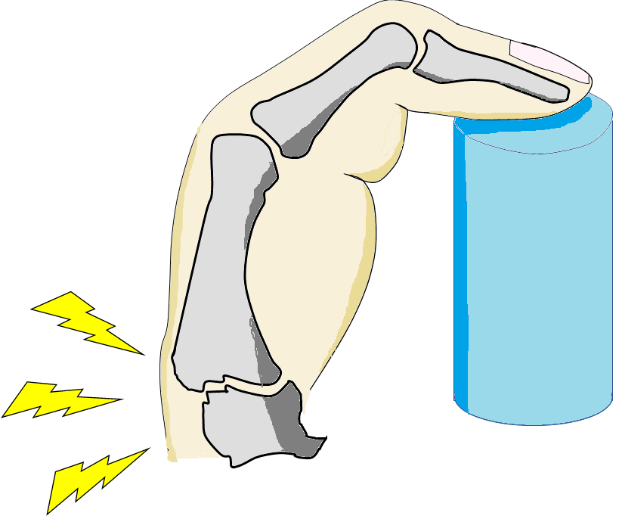

ものをつまむ時や瓶やペットボトルのふたを開ける時に痛みがあります。進行するとCM関節が背側(指の甲側)に亜脱臼し母指の外転(母指を開くこと)が制限され、MP関節(CM関節の一つ末梢の関節)過伸展、IP関節(最も先端の関節)屈曲位の母指スワンネック変形(ダックネック変形)が生じます。

- ▼つまみ動作時の母指の付け根の痛み